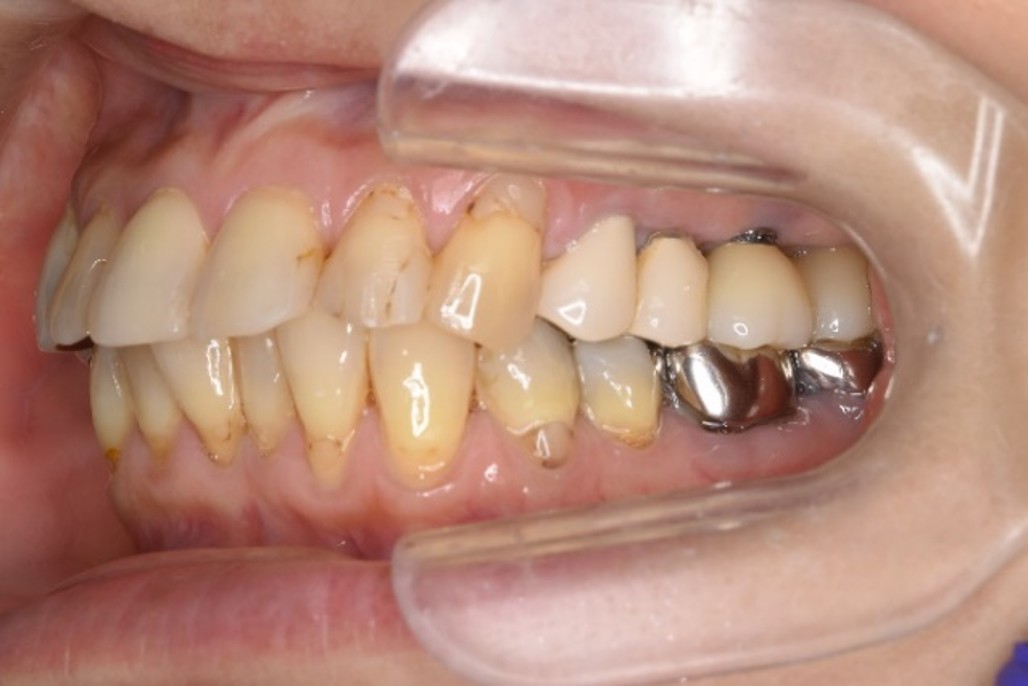

治療前